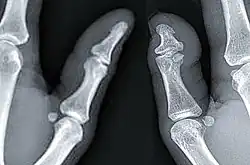

Braquidactilia tipo D unilateral, mostrando la diferencia entre un pulgar normal (pulgar izquierdo) y un pulgar afectado con braquidactilia tipo D (pulgar derecho). | ||

Se caracteriza principalmente por la presencia inofensiva de un pulgar corto y ancho el cual esta acompañado de una uña corta y ancha. En algunos casos, el dedo gordo del pie también puede estar afectado.[1]

La braquidactilia tipo D es una condición esquelética que es causada por la fusión parcial o cierre prematuro de la placa de crecimiento de la falange distal del pulgar, dejando como consecuencia una falange distal congénitamente corta, esta condición puede presentarse unilateralmente o bilateralmente.[3]